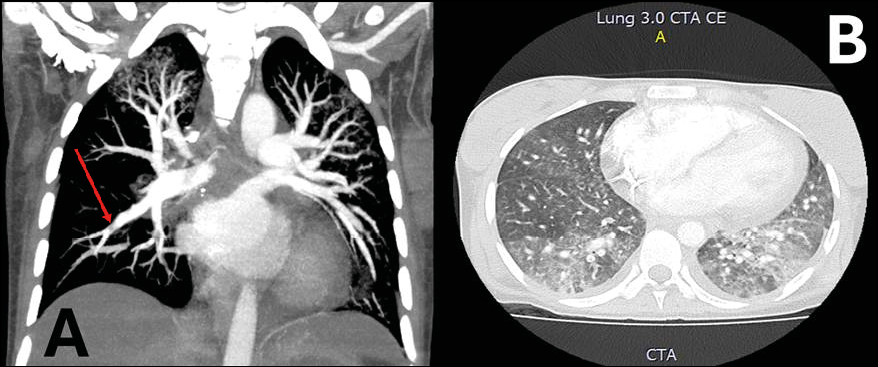

During hospitalization, the patient developed sudden dyspnea and oxygen desaturation, prompting the initiation of invasive mechanical ventilation. A pulmonary angiotomography (Figures 1a and 1b) revealed pulmonary interstitial infiltrates, pulmonary thromboembolism, and deep vein thrombosis. Full-dose anticoagulation therapy was started accordingly.

Figure 1 - Pulmonary Angiotomography: Coronal (A) and Axial (B) images. A. Central filling defect in the branches of the basal segment of the right lower lobe, with signs of a “lane” indicative of pulmonary thromboembolism. B. Interstitial involvement in medial areas with a ground-glass appearance.